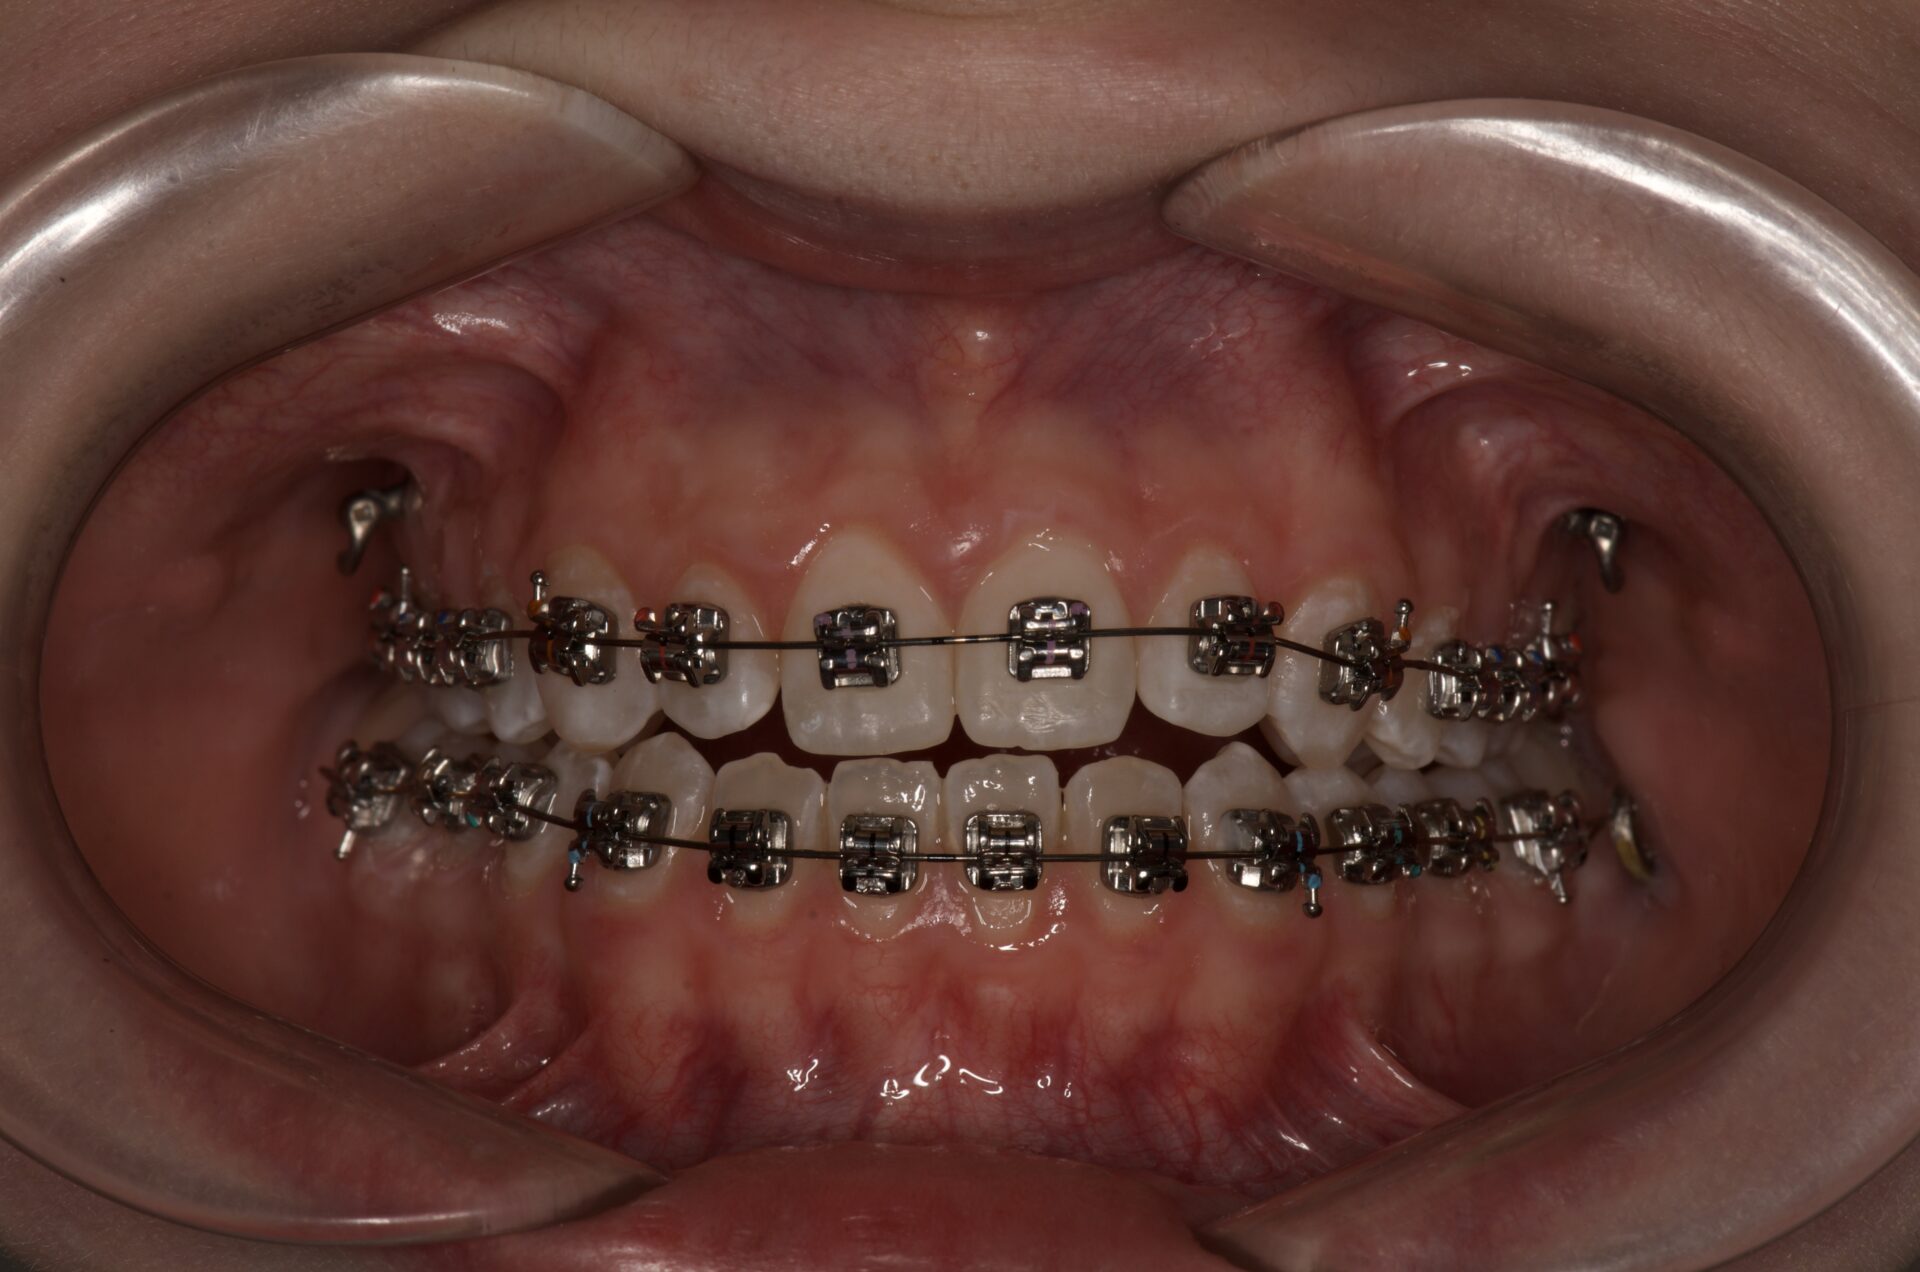

Ezen találkozás során kezelőorvosod a fogaidra rögzíti a bracketeket, és szükség esetén kiegészítő elemeket csatlakoztat a készülékedhez. Gondozási készletet kapsz fogkefével, viasszal és tippekkel, hogy tisztán tudd tartani és kényelmesen viselhesd a fogszabályozódat. 4-6 hetente az orvosod aktiválja a fogszabályozó készülékedet, hogy fogaid az előzetes terv szerint mozogjanak. Az időnként szkennelések segítségével a Segatto Face Center csapata nyomon követi a kezelés haladását és biztosítja, hogy a készüléked hatékonyan működjön.

Mosolyod egy befektetés és a Segatto Face Center csapata ezt komolyan veszi – így a bracketek, a kiegészítő elemek eltávolítása- és fogaid polírozása után retenciós készülékeket biztosítanak számodra: egy rögzített fém ívet, az elülső fogaid belső felszínére és egy kivehető készüléket, éjszakai viselésre. A kezelőorvosod elkészíti a befejező fotókat és szkenneket, hogy bemutassa az átalakulásodat. Ezt követően megtanítja, hogyan gondoskodj a retenciós készülékeidről. Részletesen átbeszéli veled a hosszú távú eredmények fenntartásához szükséges ellenőrzések fontosságát és gyakoriságát.